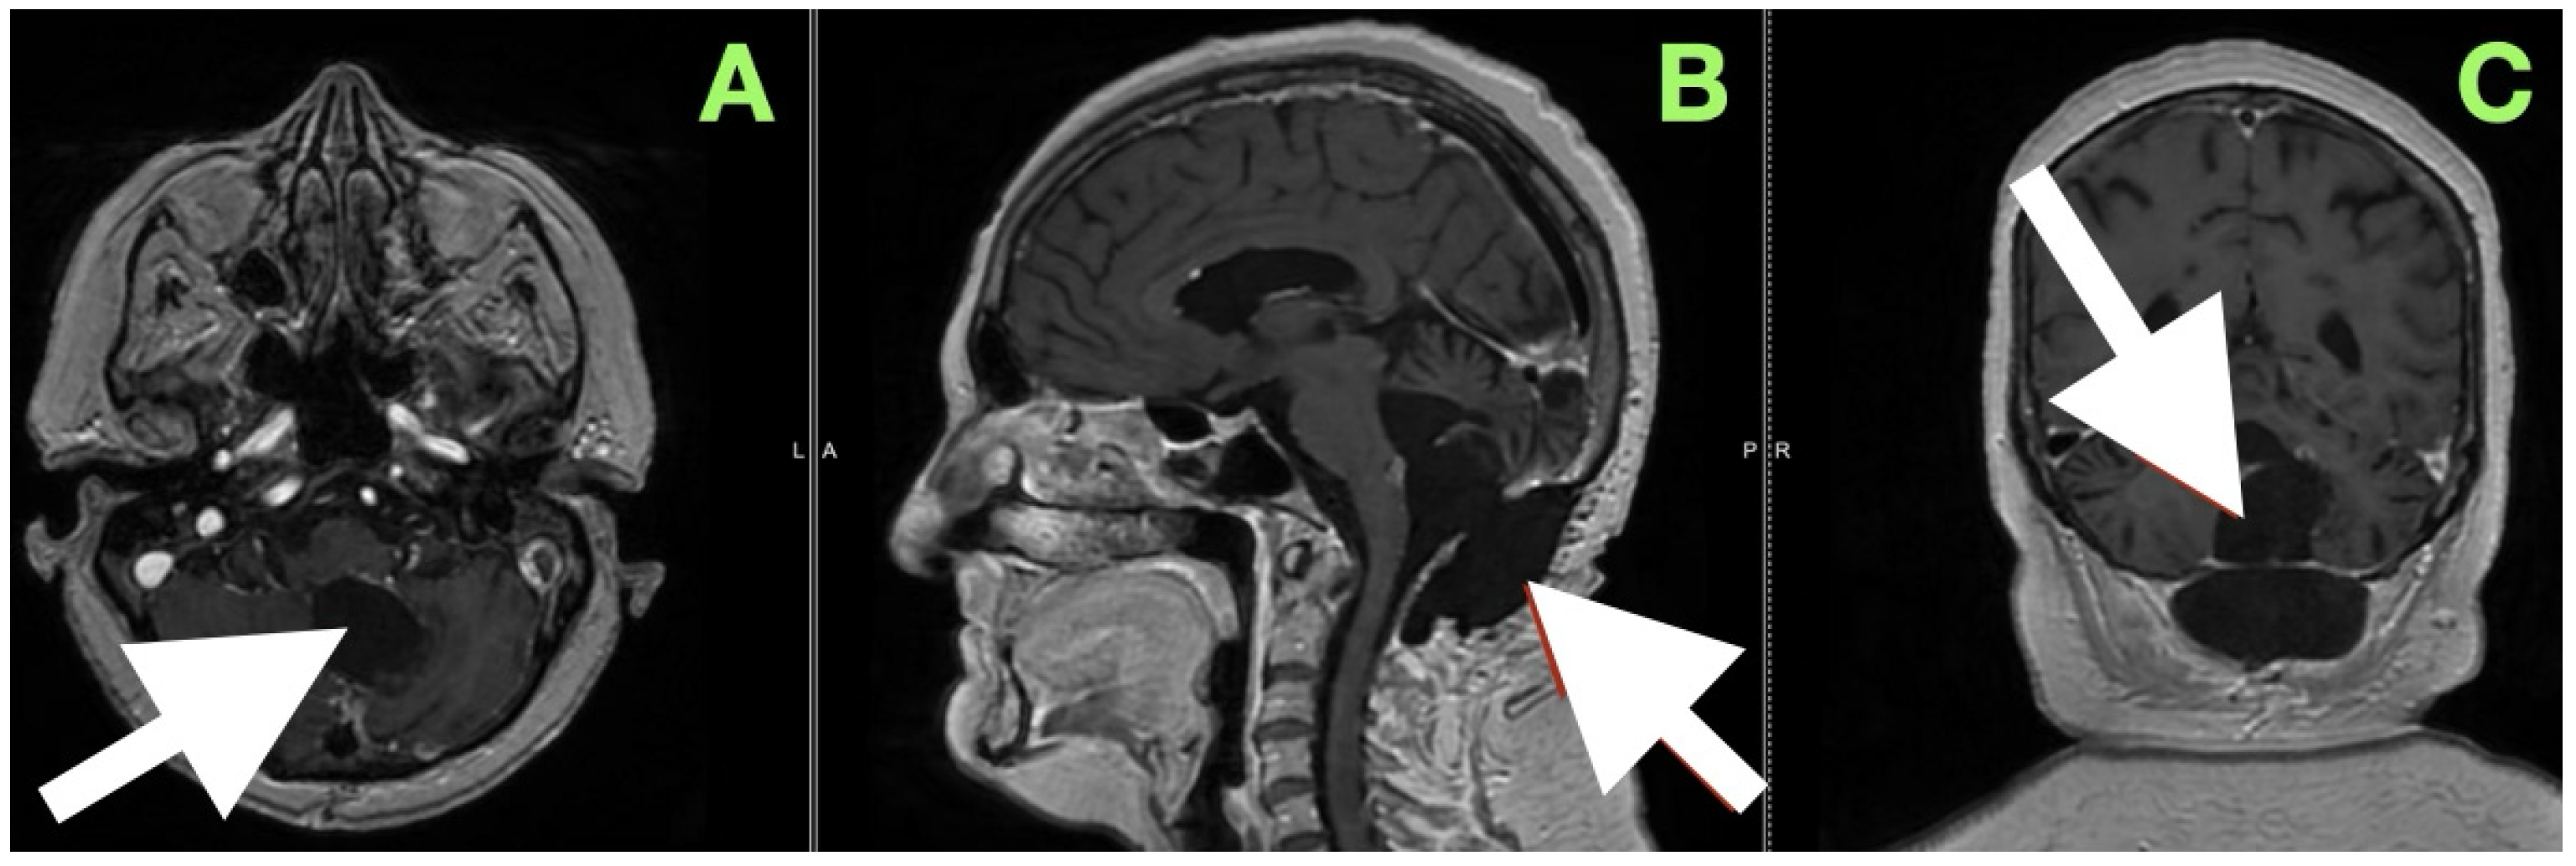

After extubation in the neurosurgical ICU postoperatively, early recovery included trunk stability, improved gaze-holding nystagmus, and less dysmetria. There were no cranial nerve impairments noted, and swallowing remained safe. Postoperative CT (Figure 3) confirmed complete decompression and re-expansion of the fourth ventricle, patency the cerebellomedullary cistern, symmetric cerebellar hemispheres, and patent foramen of Magendie. There was no presence of hemorrhage, infarction or hydrocephalus, and the operative cavity duplicated the original tumor size, underscoring the painstaking extra-axial dissection while maintaining parenchymal margins.

An immediate postoperative MRI (Figure 4) was performed to assess the resection extent and surgical purpose. Multiplanar T1-weighted sequences showed a sharply demarcated postoperative cavity; the fourth ventricle had expanded, all cerebrospinal fluid paths were unobstructed, and there was no abnormal enhancement seen. The imaging findings served as direct visual proof for the intraoperative aims, namely, decompression of the brainstem, anatomical re-establishment of the cisterns, and maintenance of surrounding neurovascular structures. No perilesional edema and no hemorrhagic debris support the use of the “stay-at-anatomy” dissection approach. Near-total resection with a midline suboccipital telovelar approach accomplished complete decompression, anatomical restoration, and preservation of all appropriate neurovascular structures. Immediate postoperative MRI demonstrated no residual mass effect or abnormal enhancement, with no imaging assessment of keratinaceous content, despite the fact that there was microbiologically adherent capsular remainder on the ventricular floor that was purposefully left intact.

Figure 3. Immediate postoperative non-contrast CT scan demonstrating complete removal of the fourth-ventricular epidermoid tumor and restoration of posterior fossa anatomy. (A) Axial view shows a well-defined postoperative cavity in the midline vermian and fourth-ventricular region, with full re-expansion of the fourth ventricle and reappearance of the cerebellomedullary cistern. The brainstem contour is normalized, and no residual mass effect or obstructive hydrocephalus is present. (B) Coronal reconstruction confirms symmetrical cerebellar hemispheres, midline restoration of the fourth ventricle, and patent foramen of Magendie, with no acute hemorrhage or postoperative edema. The surgical cavity follows the anatomical boundaries of the preoperative lesion, reflecting precise extra-axial microsurgical dissection and preservation of surrounding neural tissue.

Figure 4. Immediate postoperative MRI. (A) Axial, (B) sagittal, and (C) coronal T1-weighted images show a postoperative cavity with complete re-expansion of the fourth ventricle and patent CSF pathways (white arrows). No abnormal enhancement or diffusion-restricted focus is present, confirming gross total resection and restoration of posterior fossa anatomy.